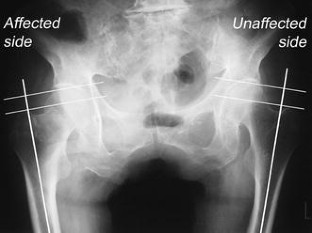

Fig. 1